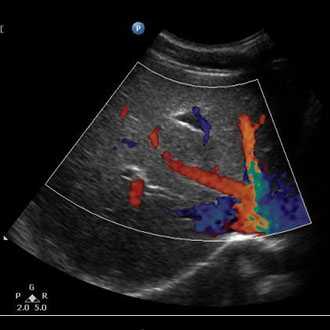

Doppler ultrasound is a special ultrasound technique that evaluates blood as it flows through a blood vessel, including the body's major arteries and veins in the abdomen, arms, legs and neck.

In an ultrasound examination, a transducer both sends the sound waves into the body and receives the echoing waves. ... Doppler ultrasound, a special application of ultrasound, measures the direction and speed of blood cells as they move through vessels.